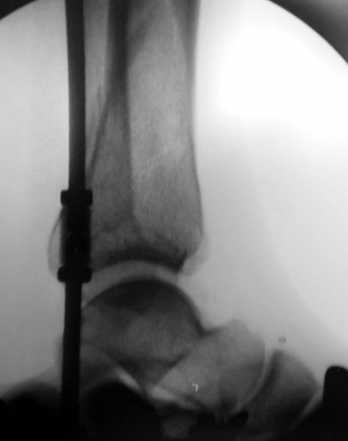

Перелом пилона 6-недельной давности

1,5 месяца назад при падении со скалы получил перелом пилона, лечился в районной больнице консервативно (циркулярная гипсовая повязка до средней 1/3 бедра). К нам попал только сегодня, сделали снимки и возник вопрос - делать ли что-то хирургически или уже пойти только на восстановительное лечение (продолжить иммобилизацию еще на 2-4 недели, потом разработка движений и т.п.)?Снимки прилагаю.

Уважаемые коллеги! Внутрисуставной перелом дистального конца б/б кости со смещением и подвывихом стопы должен был лечиться оперативно в раннем сроке.

По поводу обсуждаемого случая - 6-недельная фиксация такого перелома значительно увеличила шансы на артроз голеностопного сустава. Дальнейшая фиксация в гипсе практически сравняет эти шансы со 100%.

Если судить по представленной рентгенограмме, то, с учетом давности травмы, операция уже вряд ли необходима. Я бы продолжил гипс и назначил хондропротекторы и витамины.

После 7 недельного консервативного лечения дистального эпи-метафиза, Pylon type (кстати неплохой сустав)перелома, вряд ли поможет операция, наложить гипс на 3 недели и начать разработку сустава, ледующие снимки подскажут время нагрузки на конечность.